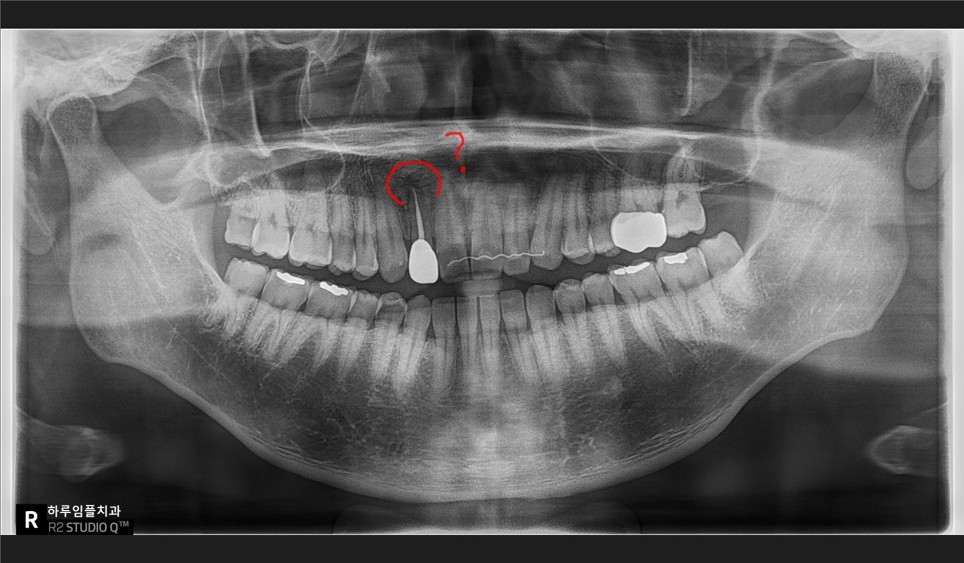

앞니 주변 잇몸에는

고름주머니가 부풀어 있었고

방사선 사진에서도

염증 부위가 선명하게 보였습니다.